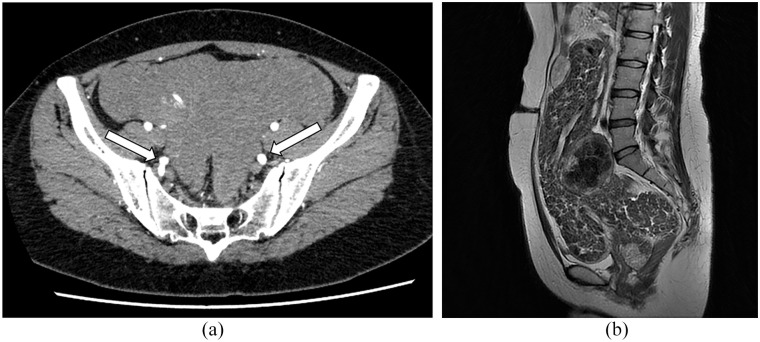

Cotyledonoid-dissecting leiomyoma, a very unusual form of uterine leiomyoma, often leads to misdiagnosis as a malignant tumor. Here, we describe a case of a 45-year-old nulliparous woman who underwent a laparoscopic biopsy of a large pelvic mass consisting of multiple flaps. Histologically, the mass was composed of smooth muscle fascicle nodules separated by hydropic connective tissue, and exhibited extensive stromal hyalinization. The tumor was diagnosed as a cotyledonoid-dissecting leiomyoma based on the laparoscopic, pathological, and image findings. Prior to performing radical laparotomy, two courses of leuprorelin were administered in anticipation of tumor reduction and hypoperfusion, and the tumor size reduced remarkably. We demonstrated the utility of laparoscopic biopsy, considering its minimal invasiveness and diagnostic accuracy. Furthermore, the preoperative use of Gonadotropin-releasing hormone (GnRH) analogs to reduce surgical stress may be useful for treating cotyledonoid-dissecting leiomyomas.